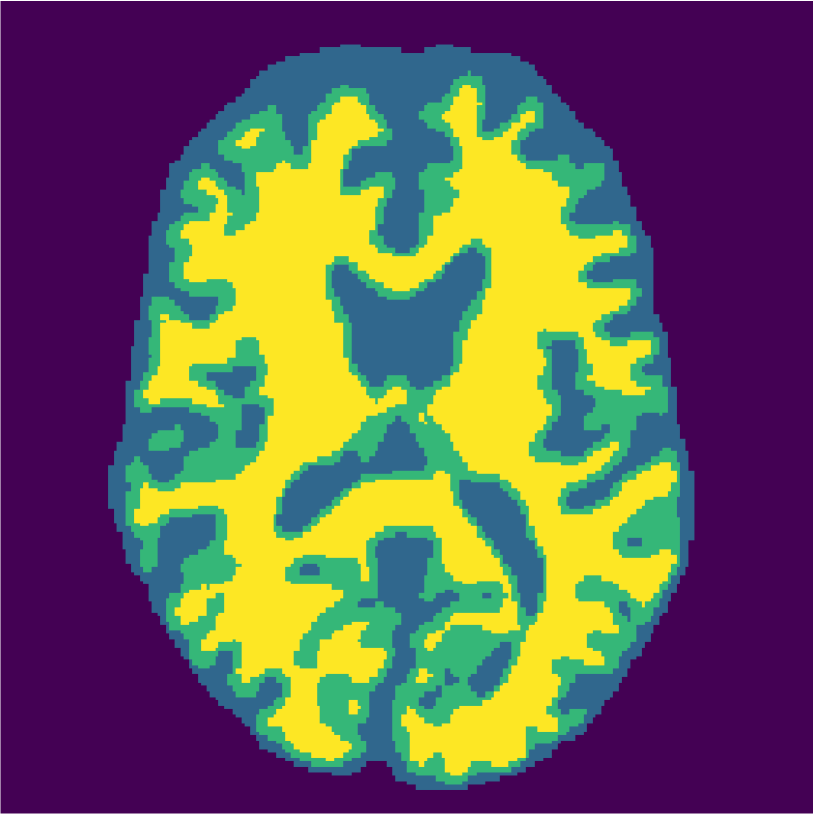

Examples of the segmentation results on one of the target test images are shown in Figure 8 for experiment 2.1, Figure 9 for experiment 2.2, and Figure 10 for experiment 2.3. Examples are shown after using 1 target patch per tissue for training, and after using 100 target patches per tissue for training. The results show that only the mrai-net classifier is able to predict a segmentation that approaches the ground truth with only 1 target patch per tissue for training (error for experiment 2.1 = 0.269, experiment 2.2 = 0.403, experiment 2.3 = 0.320), while the source and target classifiers cannot (source error for experiment 2.1 = 0.667, experiment 2.2 = 0.653, experiment 2.3 = 0.435; target error for experiment 2.1: 0.591, experiment 2.2: 0.614, experiment 2.3 = 0.596). After using 100 patches the source and target classifiers can predict a gross segmentation of WM, GM and CSF (source error for experiment 2.1 = 0.213, experiment 2.2 = 0.384, experiment 2.3 = 0.363; target error for experiment 2.1: 0.205, experiment 2.2: 0.368, experiment 2.3 = 0.368), but the mrai-net classifier prediction shows more details and a lower tissue classification error (error for experiment 2.1 = 0.111, experiment 2.2 = 0.276, experiment 2.3 = 0.284).

2.3) Experiment on 3.0T simulated data and 3.0T real data (Source: Brainweb3.0T, Target: MRBrainS).